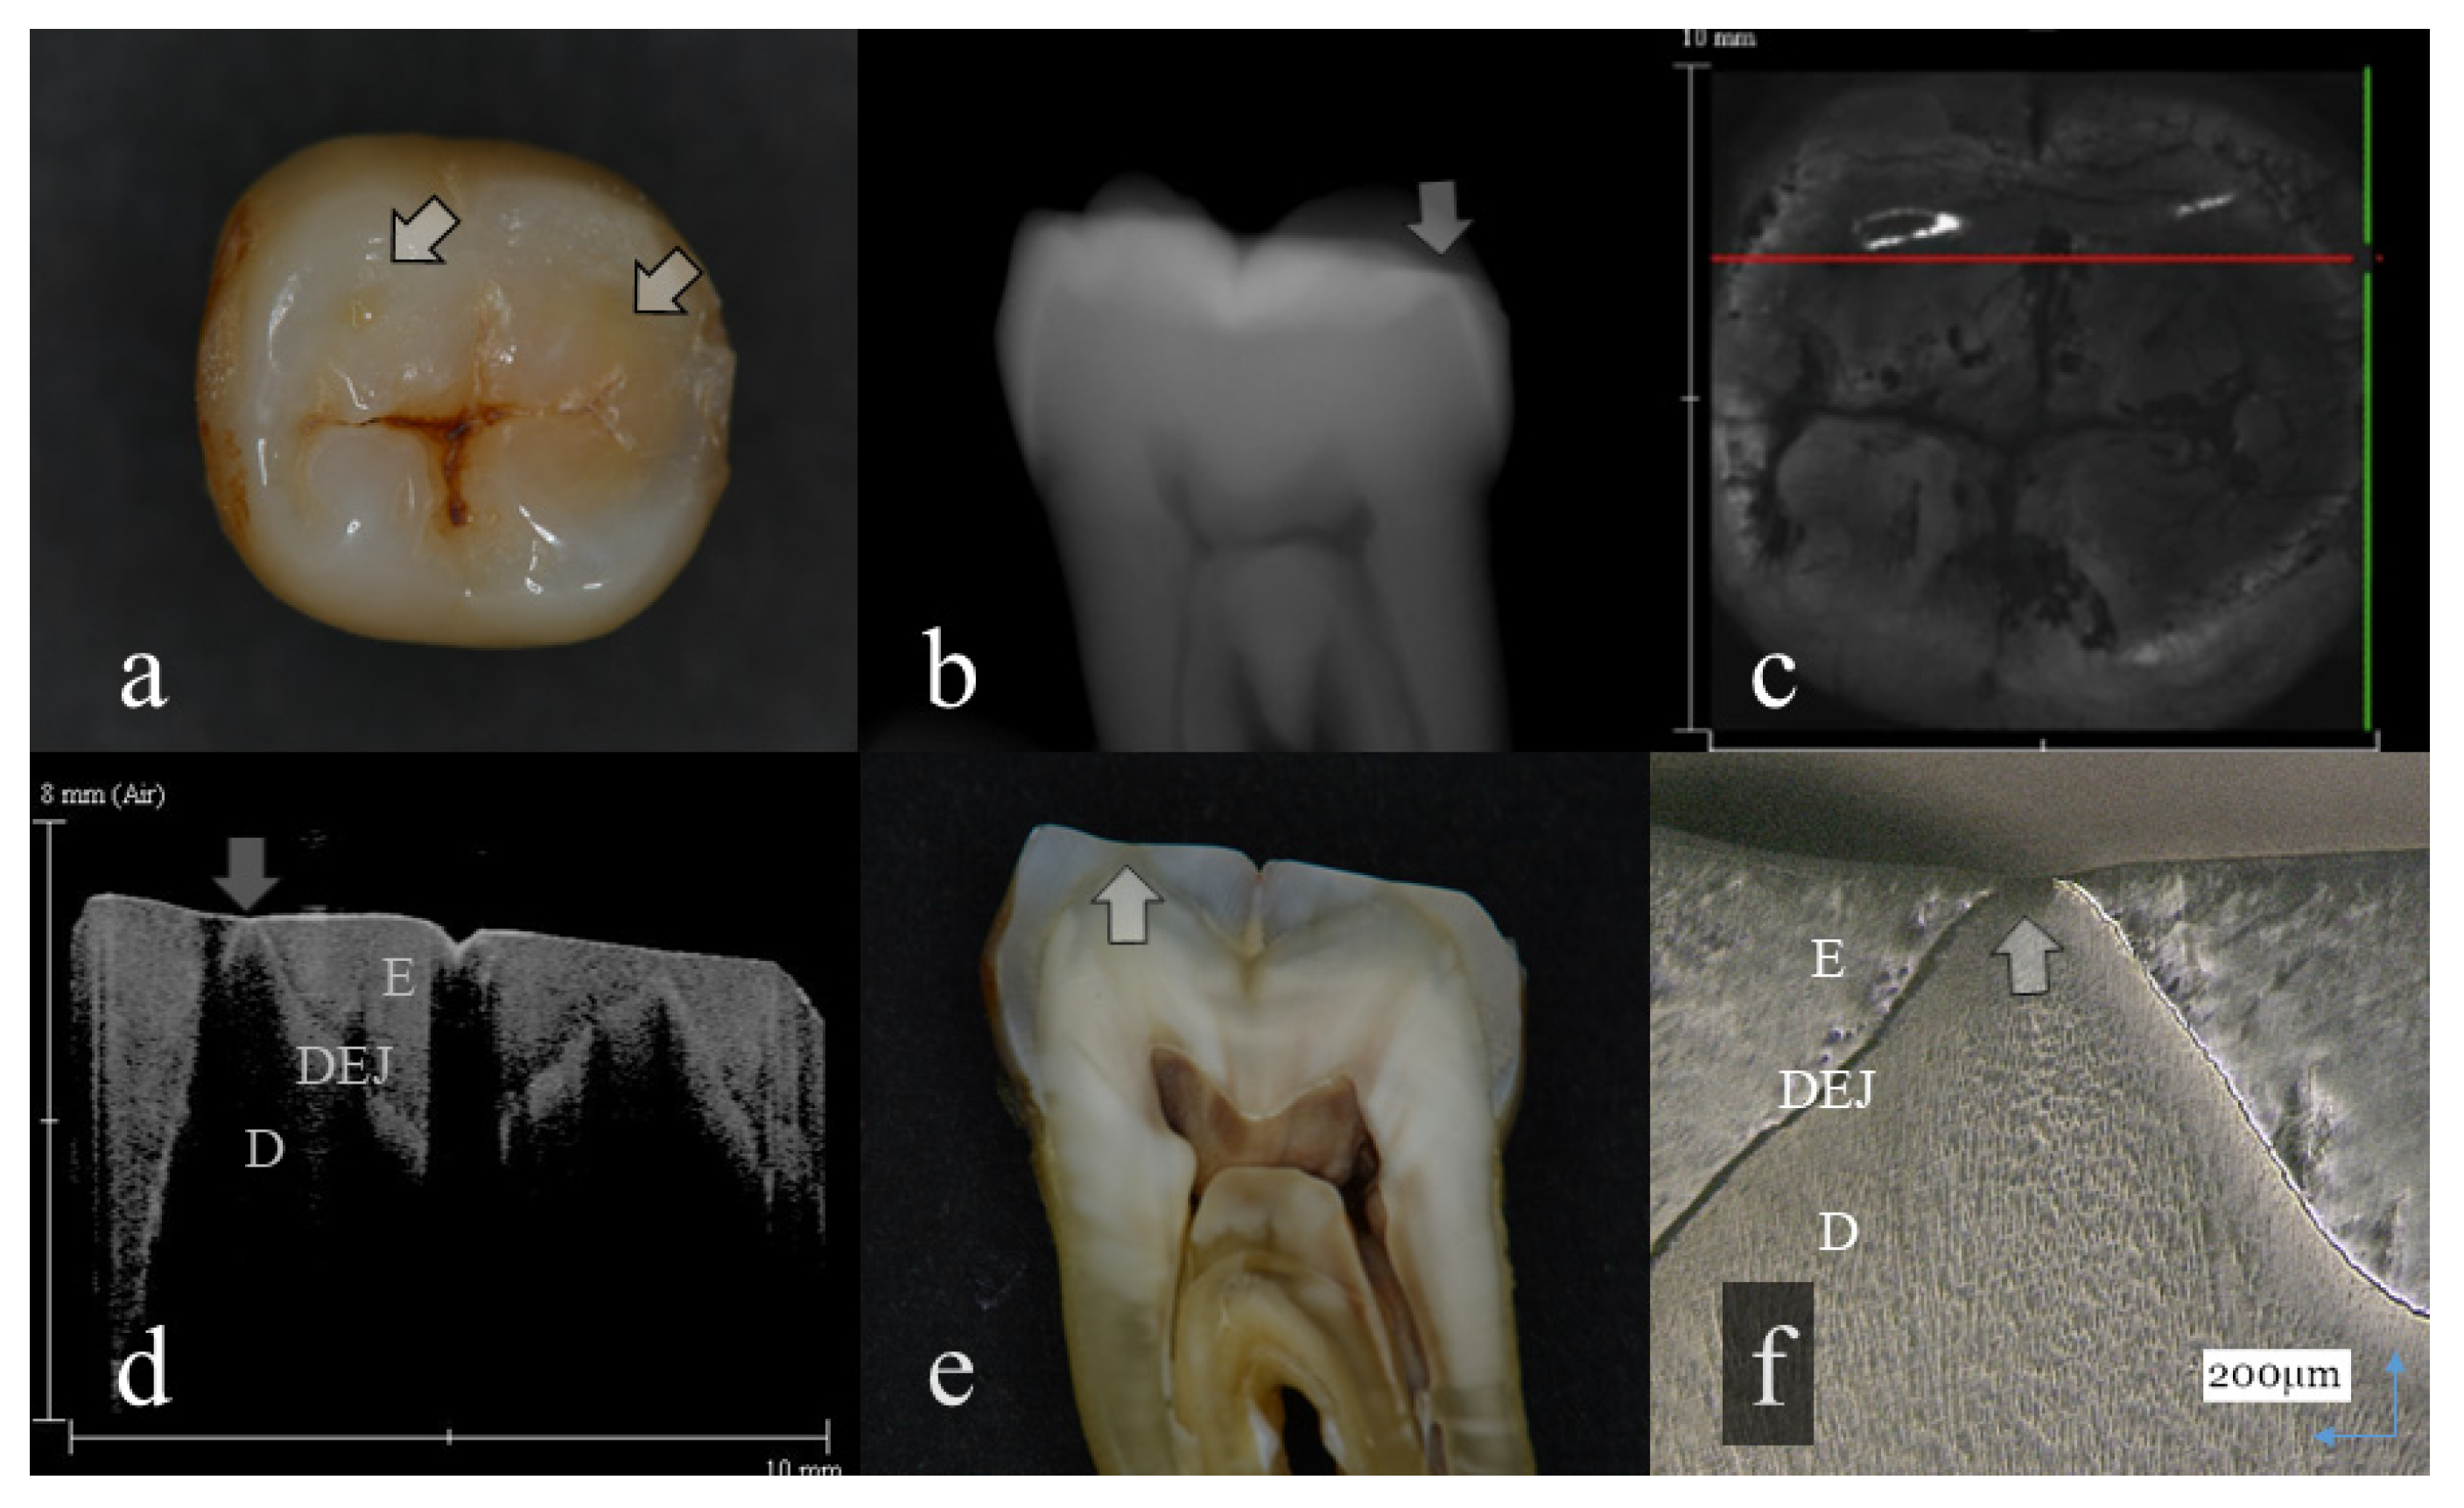

- Score 1: Slight enamel wear. Initial tooth wear was within the enamel and more than 1/2 thickness of enamel left.

- Score 2: Distinct enamel wear. Tooth wear was within the enamel and less than 1/2 thickness of enamel left.

- Score 3: Tooth wear with slight dentin exposure. Tooth wear reached to the dentin-enamel junction (DEJ). Dentin exposure was slight with less than 1 mm diameter.

- Score 4: Tooth wear with involvement of dentin. Tooth wear was beyond the DEJ to cause dentin exposure. The diameter of dentin exposure was more than 1 mm.